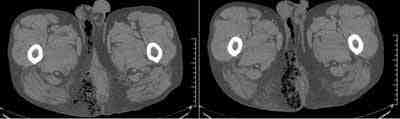

Caso 1: Varón de 50 años sin antecedentes patológicos de interés salvo obesidad, consultó por proctalgia y tumoración anal de días de evolución, en analítica presentaba datos de sepsis. Se realizó TC de pelvis urgente, sin contraste endovenoso, que demostró gas en región isquiorrectal derecha con extensión en herradura a raíz del escroto (figura 1), Se realizó drenaje y desbridamiento con buena evolución en planta hasta alta.

Figura 1: Reconstrucciones coronales muestran gas en región isquiorrectal derecha

Caso 3: Varón de 49 años con antecedentes de hepatopatía enólica y obesidad. Acude a urgencias por proctalgia y tumoración perianal de 3 días de evolución, con fiebre, en analítica presenta leucocitosis, neutrofilia y alteración de coagulación. Se realiza TC urgente sin contraste intravenoso, mostrando abundante gas en fosa isquiorrectal derecha, con tumefacción de partes blandas (figura 3). Con diagnóstico de gangrena de Fournier se realiza cirugía urgente. Tras sucesivas curas, con buena evolución en planta es dado de alta.

Figura 3: abundante gas en región isquiorrectal derecha